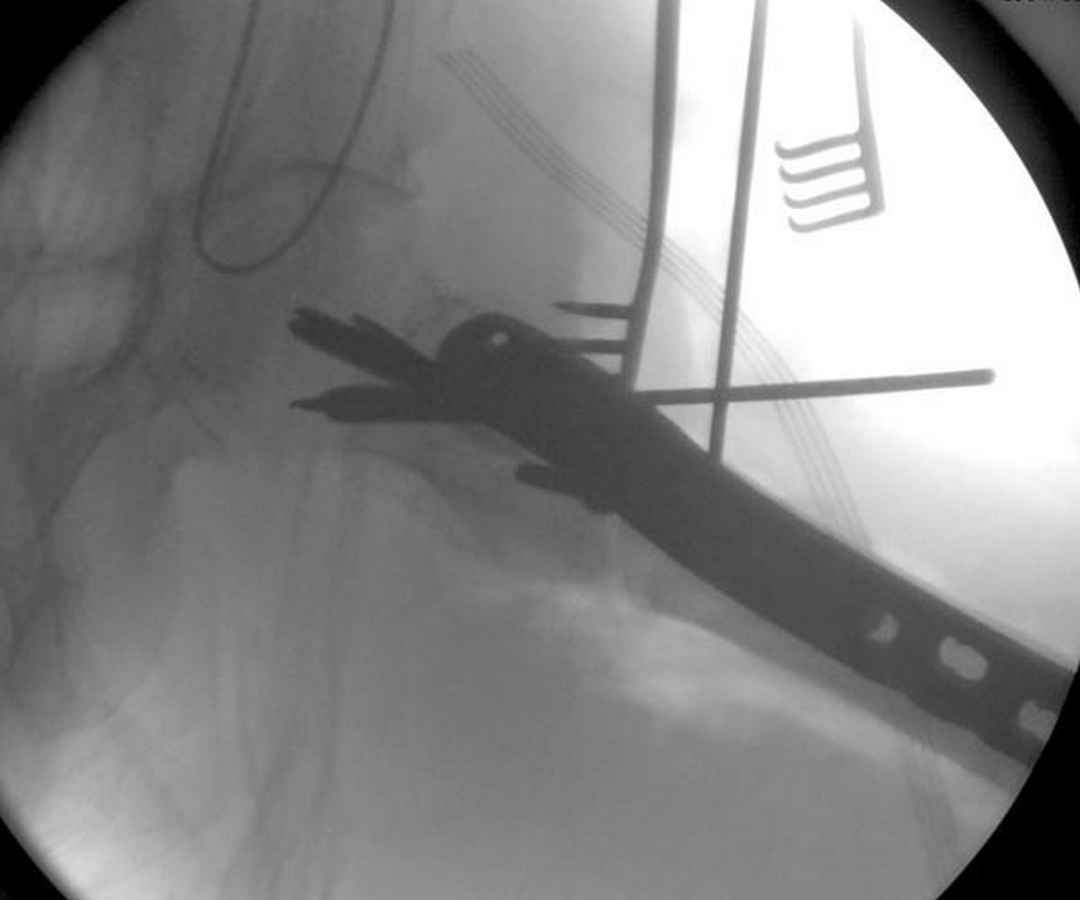

Здесь 83 года, травма в результате падения

судя по картинкам с ЭОПа явно использовались приемы непрямой репозиции под его контролем, а так же интраоперационный ЭОП-контроль положения винтов, без такого контроля операция может ухудшить ситуацию (опять же учтите сроки) т.к. результат буде зависеть в большей степени от искусства хирурга, а не от технологии